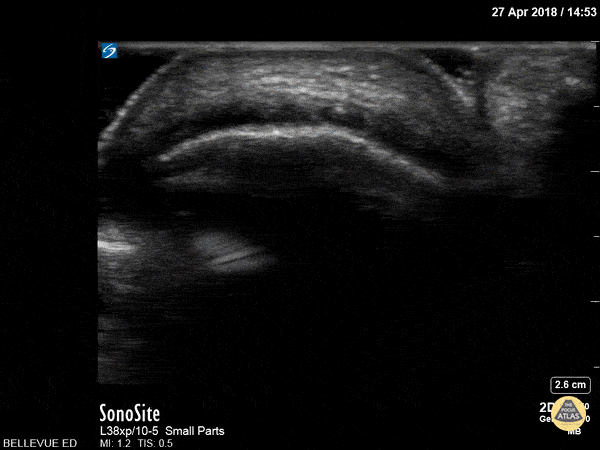

Musculoskeletal - Achilles Tendon Short Axis

This clip begins with the soft tissue of the heel and calcaneus visible in short axis. As the probe moves proximally, the achilles tendon appears in transverse view as an oval with an echogenic punctate appearance beneath a bright layer of skin at the top of the screen. As we move proximally the achilles tendon tapers and the gastrocnemius/soleus muscle complex becomes more prominent. Hannah Kopinksi and Dr. Lindsay Davis - NYU Emergency Medicine